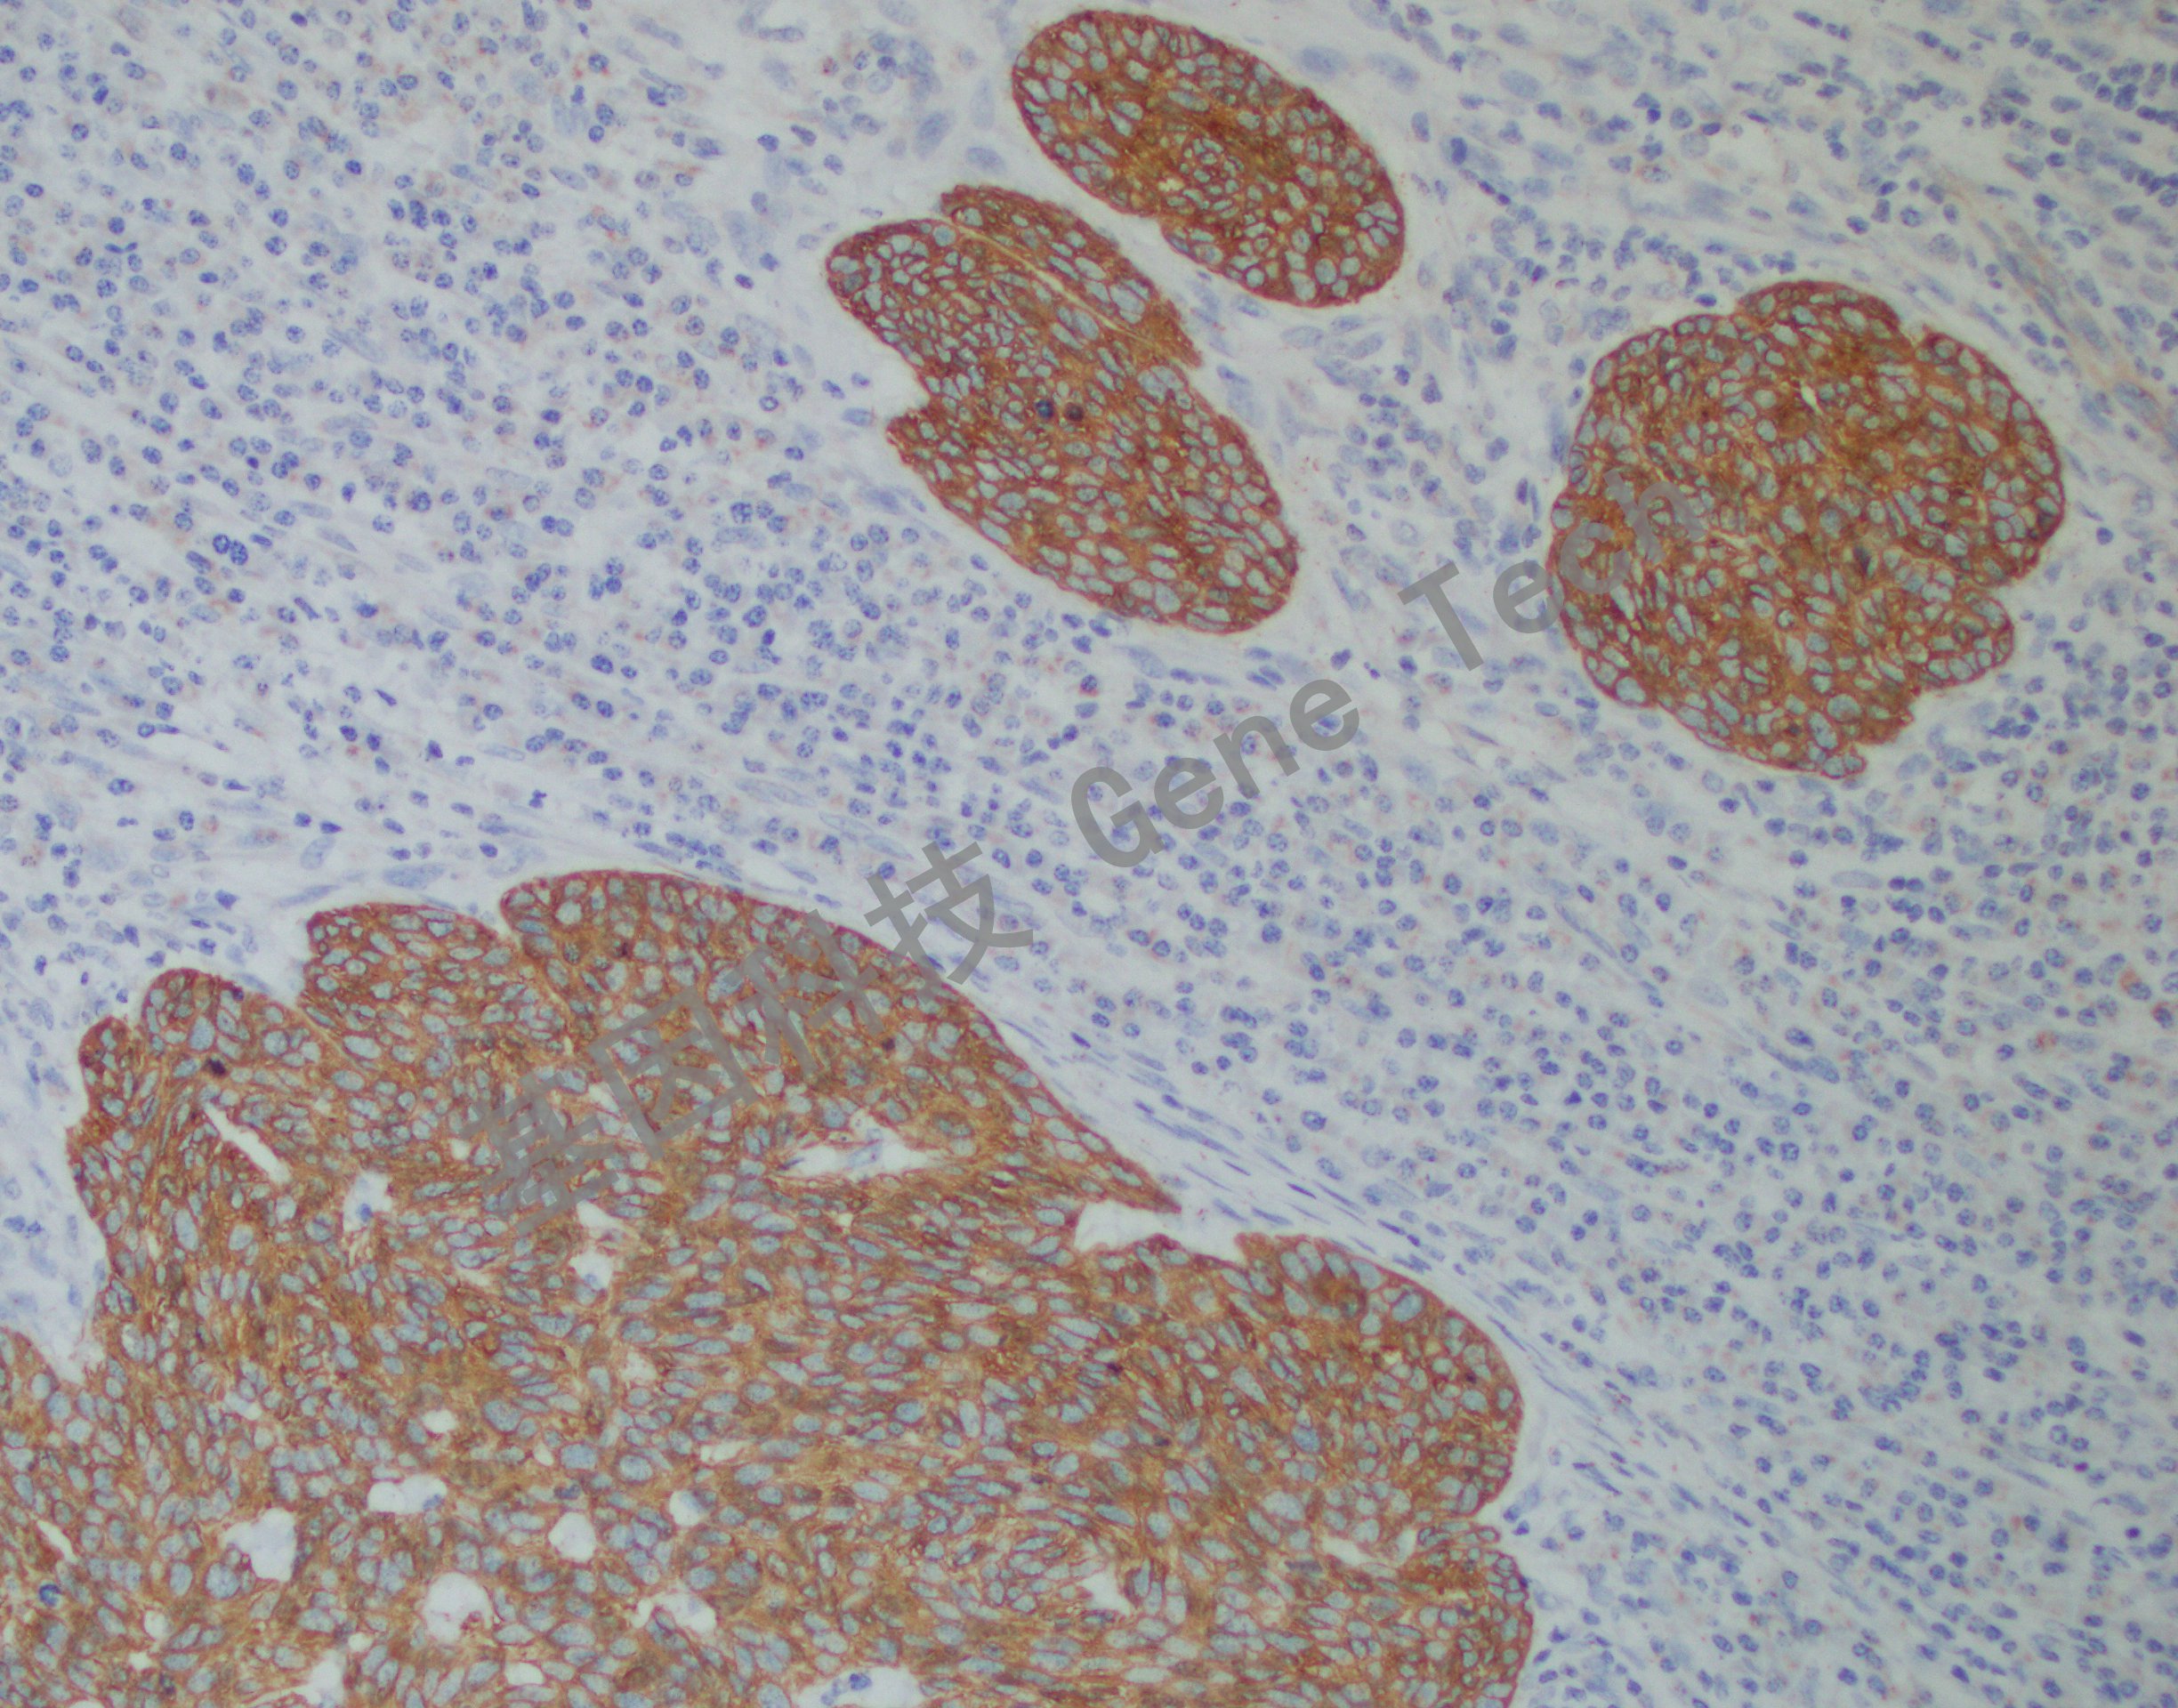

皮肤石蜡切片,用 CK17(GM7046)染色,细胞浆阳性,DAB 显色。

正常组织中,CK17 主要表达于复层上皮和假复层上皮的基底细胞以及部分腺体( 如唾液腺) 的肌上皮细胞中。该抗体主要用于肺、子宫颈和口腔鳞状细胞癌的诊断。